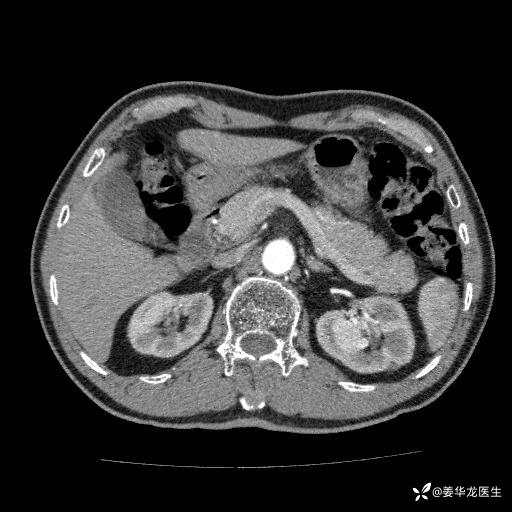

左肾中心型肾门部肿瘤39mm×34mm×36mm,右肾GFR25ml/min,部分切还是全切?

患者75岁老年男性,体重50kg,无高血压、肾病、糖尿病等基础病,检查发现左肾中心型肾门部肿瘤,右肾GFR只有25ml,无肉眼血尿,无镜下血尿。入院验血常规检查均正常,包括肾功能,肌酐102.7umol/L.

二、左肾肿瘤与左肾集合系、左肾动静脉关系密切,左肾部分切除术可行吗?成功率有多大?成功部分切后,肾功能还有多少?